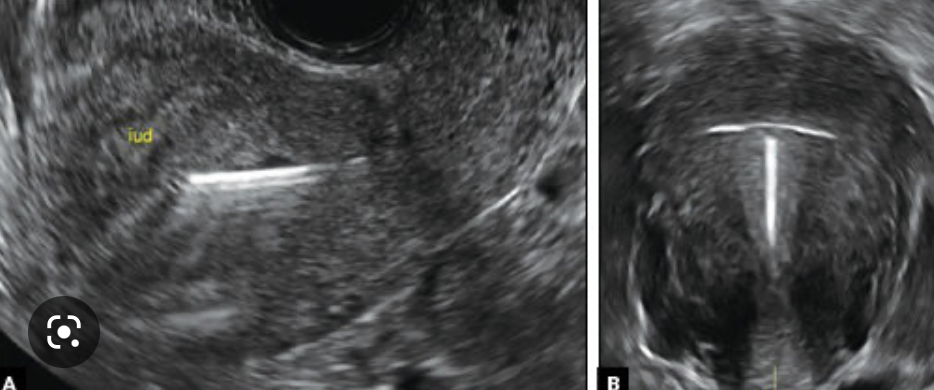

What is the first line investigation when coil strings cannot be palpated?

A

ultrasound

• this can be used to confirm the correct placement of the IUD within the uterine cavity